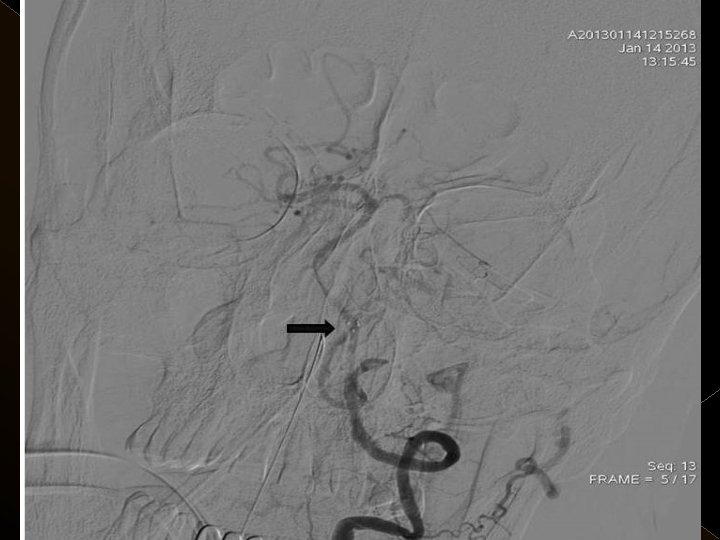

� İnme tedavisinde iv tpa uygulamasını takiben � intraarteriyel (İA) trombolitik tedavi (ia tpa ve ia mekanik trombolizis) � İA stent yardımı ile trombektomi yöntemleri kullanılarak tedaviye cevap ve komplikasyonlar araştırıldı.

KOMPLİKASYONLAR Ponksiyon bölgesi komplikasyonları � Trombektomi stentine ait komplikasyon (*1) � Diseksiyon(*2) � Karotikokavernöz fistül (‘ 1) � Hemorajik komplikasyonlar(‘ 5) Semptomatik-nonsemptomatik � İskemik komplikasyonlar (3) � Reoklüzyon (2 i. a) � Kontrast madde nefropatisi �